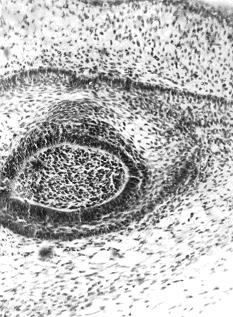

В контроле эмалевые органы длинной тонкой шейкой соединялись с зубной пластинкой. Они глубоко охватывали зубные сосочки, клетки которых образовывали два, три куполообразных вдавления в эмалевый орган. Клетки внутреннего эмалевого эпителия располагались в несколько слоев. Большинство их лежало на основной мембране. Многорядность наружного эмалевого эпителия была выражена слабее, чем внутреннего, местами он имел четкое однослойное строение. Пульпа эмалевого органа была рыхлой, с хорошо различимыми веретенообразными и звездчатыми клетками. У подопытных животных в некоторых крупных эмалевых органах с формирующимися двумя зубными сосочками встречались очаговые скопления клеток в виде утолщения не только во внутреннем эмалевом эпителии, но и в неистонченном наружном. Соответственно им клетки пульпы лежали более компактно (рис. 1).

Рис. 1. Очаговое утолщение в области наружного и внутреннего эмалевого эпителия. Опыт. Окраска гематоксилином и эозином. Ув. 200